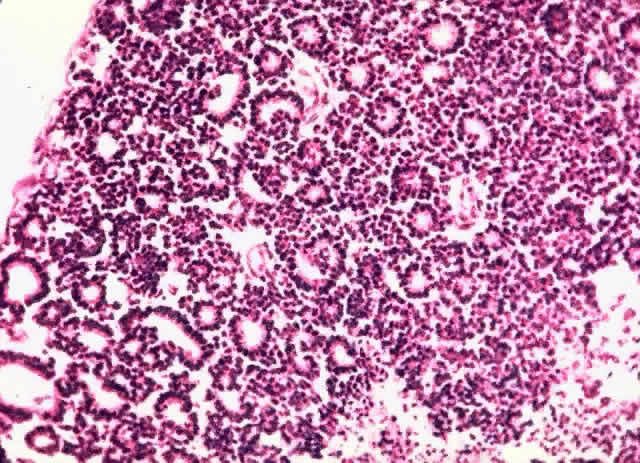

Tumor rosettes were described by Flexner91 in 1881 and Wintersteiner92 in 1897. Multinucleated tumor cells probably represent regression.93 Flexner-Wintersteiner and Homer-Wright rosettes may be seen (Figs. 5 and 6). Flexner-Wintersteiner rosettes are lined with cuboidal cells that have terminal bars at the apical ends, creating a central lumen. These represent an attempt at retinal differentiation set in a field of undifferentiated cells. Homer-Wright rosettes are less characteristic of retinoblastoma. They are associated with medulloblastoma. The cells are arranged around a central tangle of cytoplasmic processes. “Fleurettes” represent a higher degree of maturation. The cells demonstrate evidence of photoreceptor differentiation in small, bouquet-like clusters (Fig. 7). Cell differentiation with fleurettes and FlexnerWintersteiner rosettes may have a better prognosis.52,94 The hereditary variant of retinoblastoma has been shown to be more highly differentiated.95

Fig. 5. Flexner-Wintersteiner rosettes (H & E, × 40).

Fig. 6. Homer-Wright rosette (H & E, × 100).